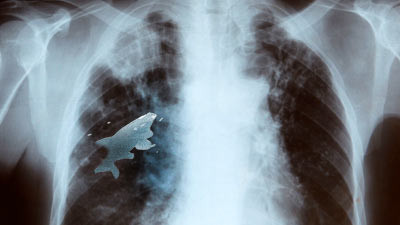

| Hình chụp X-quang cho thấy con cá đang "bơi lội" ở lồng ngực Anil. |